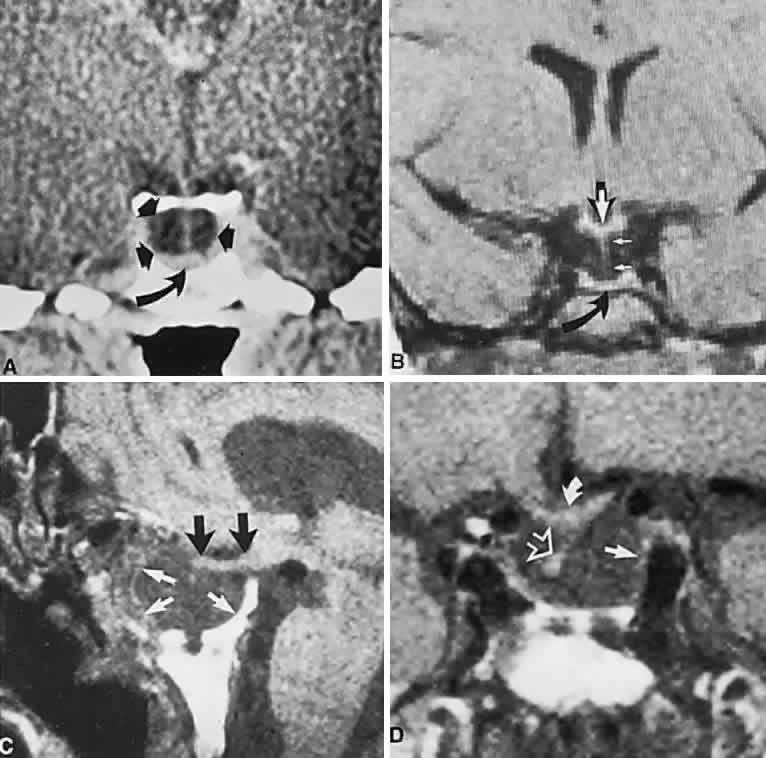

Fig. 3. Neuroimaging of pituitary adenomas. A. Axial computed tomography (CT) section shows a round tumor mass filling the suprasellar cistern; ring enhancement (arrows) indicates subcapsular hemorrhage. B. Contrast-enhanced coronal CT section through a large invasive adenoma. Note encasement of the carotid artery (arrows) and the position of the middle cerebral artery above (arrowheads). C. Axial CT section shows lateral expansion into the cavernous sinuses (white arrows) and a necrotic cyst (black arrow). D. Subfrontal superior extent of the mass. Note the middle cerebral arteries. E. Magnetic resonance imaging of a large lobulated prolactinoma, with suprasellar extension. Note the distortion of the third ventricle (open arrows) and extension toward the temporal lobe (long arrow); the tumor has not involved the sphenoidal sinus (s). F. Chiasm (arrowheads) is draped on the superior surface of the tumor (TR, 550 milliseconds; TE, 26 milliseconds). G. Sagittal section shows suprasellar growth with the chiasm above (arrowheads); the sella (arrows) and sphenoidal sinus (s) are normal (TR, 850 milliseconds; TE, 26 milliseconds). H. Hyperintense signal (TR, 2000 milliseconds; TE, 60 milliseconds) indicates the partial cystic character. Sagittal (I) and axial (J) sections with head tilt to the right, in case of a large cystic adenoma with an interface level between newer blood (white arrow) and older blood (black arrow) (TR, 800 milliseconds; TE, 30 milliseconds). K. Signal difference is intensified (TR, 2100 milliseconds; TE, 80 milliseconds). L. Hemorrhage (bright signal, arrow) in a pituitary adenoma with headache and bitemporal field depressions. M. Without interventions, 2-month follow-up showed spontaneous involution, with normal pituitary gland (arrow), stalk, and chiasm.